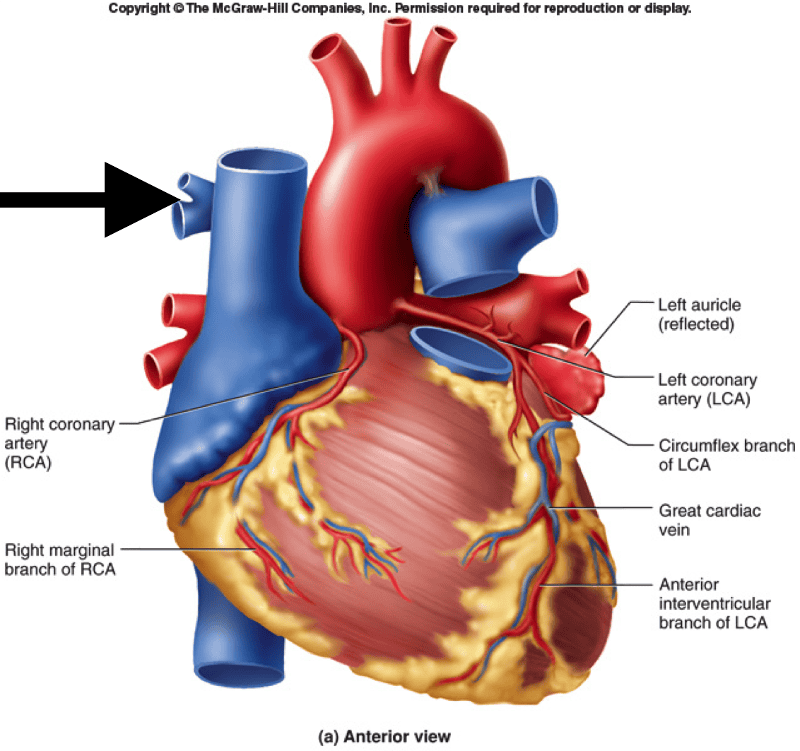

Print KINS 294 Final Exam flashcards | Easy Notecards

Isolated Disease of the Ostium Left Anterior Descending or Circumflex …

Isolated Disease of the Ostium Left Anterior Descending or Circumflex …

The fifteen segments of coronary arteries. LM: Left main coronary; LAD …

Cardiophysiology